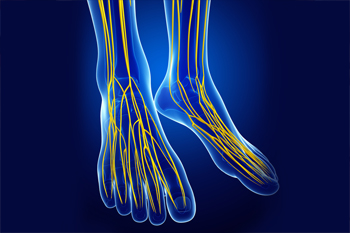

Charcot Marie Tooth Disease and the Feet

Charcot Marie Tooth (CMT) disease is a neurological condition characterized by a weakness and loss of sensation in the legs, hands, and feet due to nerve damage. This condition is genetic, affecting approximately 1 in every 2500 people. CMT develops gradually over time and progressively worsens. While there is no cure, a podiatrist can help you manage the symptoms of CMT in your feet. People with this condition may experience a change in the structure of their feet, developing high arches and hammertoes. Pain, muscle weakness, altered sensation, and muscle cramps are also common. Your podiatrist may recommend a treatment program consisting of foot strengthening and stretching exercises, orthotics, pain medication, and possibly surgery to reduce symptoms and maintain your mobility and quality of life. If you suffer from CMT disease, seeing a podiatrist can help.

Neuropathy

Neuropathy can be a potentially serious condition, especially if it is left undiagnosed. If you have any concerns that you may be experiencing nerve loss in your feet, consult with Kevin Powers, DPM from The Center for Lower Extremity Nerve Surgery. Our doctor will assess your condition and provide you with quality foot and ankle treatment for neuropathy.

What Is Neuropathy?

Neuropathy is a condition that leads to damage to the nerves in the body. Peripheral neuropathy, or neuropathy that affects your peripheral nervous system, usually occurs in the feet. Neuropathy can be triggered by a number of different causes. Such causes include diabetes, infections, cancers, disorders, and toxic substances.

Symptoms of Neuropathy Include:

- Numbness

- Sensation loss

- Prickling and tingling sensations

- Throbbing, freezing, burning pains

- Muscle weakness

Those with diabetes are at serious risk due to being unable to feel an ulcer on their feet. Diabetics usually also suffer from poor blood circulation. This can lead to the wound not healing, infections occurring, and the limb may have to be amputated.

Treatment

To treat neuropathy in the foot, podiatrists will first diagnose the cause of the neuropathy. Figuring out the underlying cause of the neuropathy will allow the podiatrist to prescribe the best treatment, whether it be caused by diabetes, toxic substance exposure, infection, etc. If the nerve has not died, then it’s possible that sensation may be able to return to the foot.

Pain medication may be issued for pain. Electrical nerve stimulation can be used to stimulate nerves. If the neuropathy is caused from pressure on the nerves, then surgery may be necessary.

Neuropathy

Neuropathy is the weakness, numbness, and pain in the hands and feet due to damage to the peripheral nerves. The peripheral nerves are responsible for sending information from the brain and spinal cord to the rest of your body. Causes of Neuropathy include: traumatic injuries, infections, metabolic problems, exposure to toxins, and diabetes.

Diabetes is the most common cause, with more than half of the diabetic population developing some type of neuropathy. There are several types of neuropathy and they vary based on the damage of the nerves. Mononeuropathy is classified as only one nerve being damaged. When multiple nerves are affected, it is referred as polyneuropathy. One of the types of polyneuropathy is distal symmetric polyneuropathy. It is the most common for people with diabetes and starts when the nerves furthest away from the central nervous begin to malfunction. The symptoms begin with pain and numbness in the feet and then they travel up to the legs. A rarer form of polyneuropathy is acute symmetrical peripheral neuropathy, which is a severe type that affects nerves throughout the body and is highly associated with Guillain-Barre syndrome, an autoimmune disorder that attacks the peripheral nervous system and can be fatal. Although there are many types of neuropathy, most of them share the same symptoms such as pain, extreme sensitivity to touch, lack of coordination, muscle weakness, dizziness, and digestive problems. Since neuropathy affects the nerves, those affected should be careful of burns, infection and falling, as depleted sensations disguise such ailments.

The best way to prevent neuropathy is to manage any medical conditions such as diabetes, alcoholism, or rheumatoid arthritis. Creating and managing a healthy lifestyle can also go a long way. Having a healthy diet full of fruits, vegetables, whole grains and lean protein can keep the nerves healthy. These types of food have the nutrients to prevent neuropathy. Regularly exercising can help as well, but it is best to consult with a doctor about the right amount. In addition to diet and exercise, avoiding risk factors will also prevent neuropathy. This includes repetitive motions, cramped positions, exposure to toxic chemicals, smoking and overindulging on alcohol.